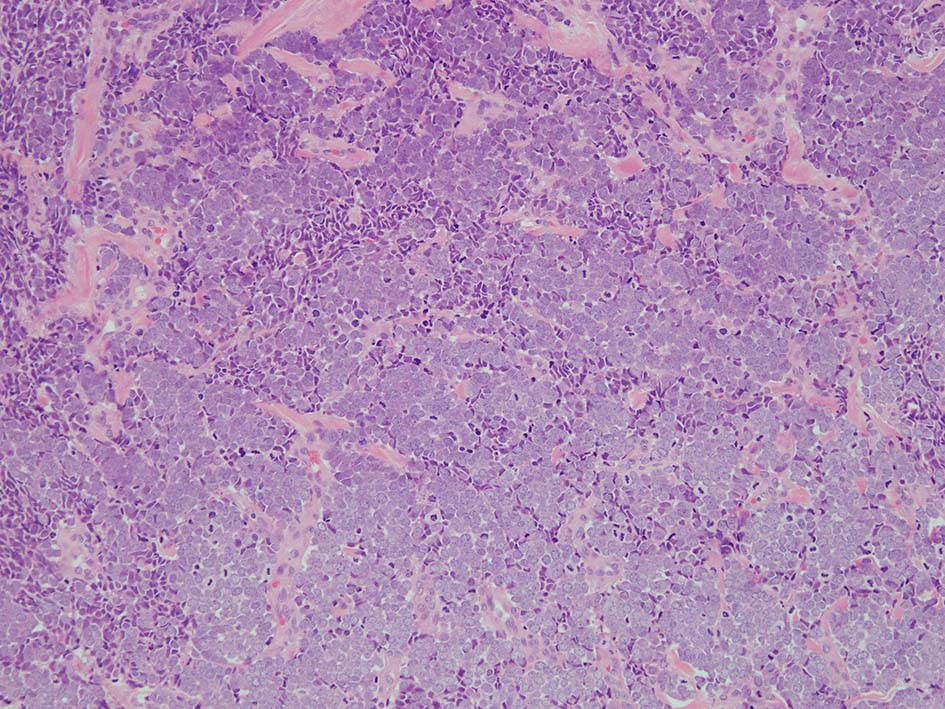

trabecular type, intermediate type, samll cell typeの3パターンの組織型に分類されているがしばしば混在している.

- trabecular typeは円形から多稜形の腫瘍細胞が索状に配列, 3形のなかで腫瘍細胞がもっとも大きく, 円形核と比較的豊富な細胞質をもつ.

- intermediate typeではtrabecular, samll cell typeの中間の腫瘍細胞サイズを示す. 組織型としてはもっとも多い.

血管を間質にしてround cellsが索状に増殖する所見. rossett様配列がある. CK20は特徴的な dot-like patternを示す. クリックで大きな画像が見られます.

HE

HEx200